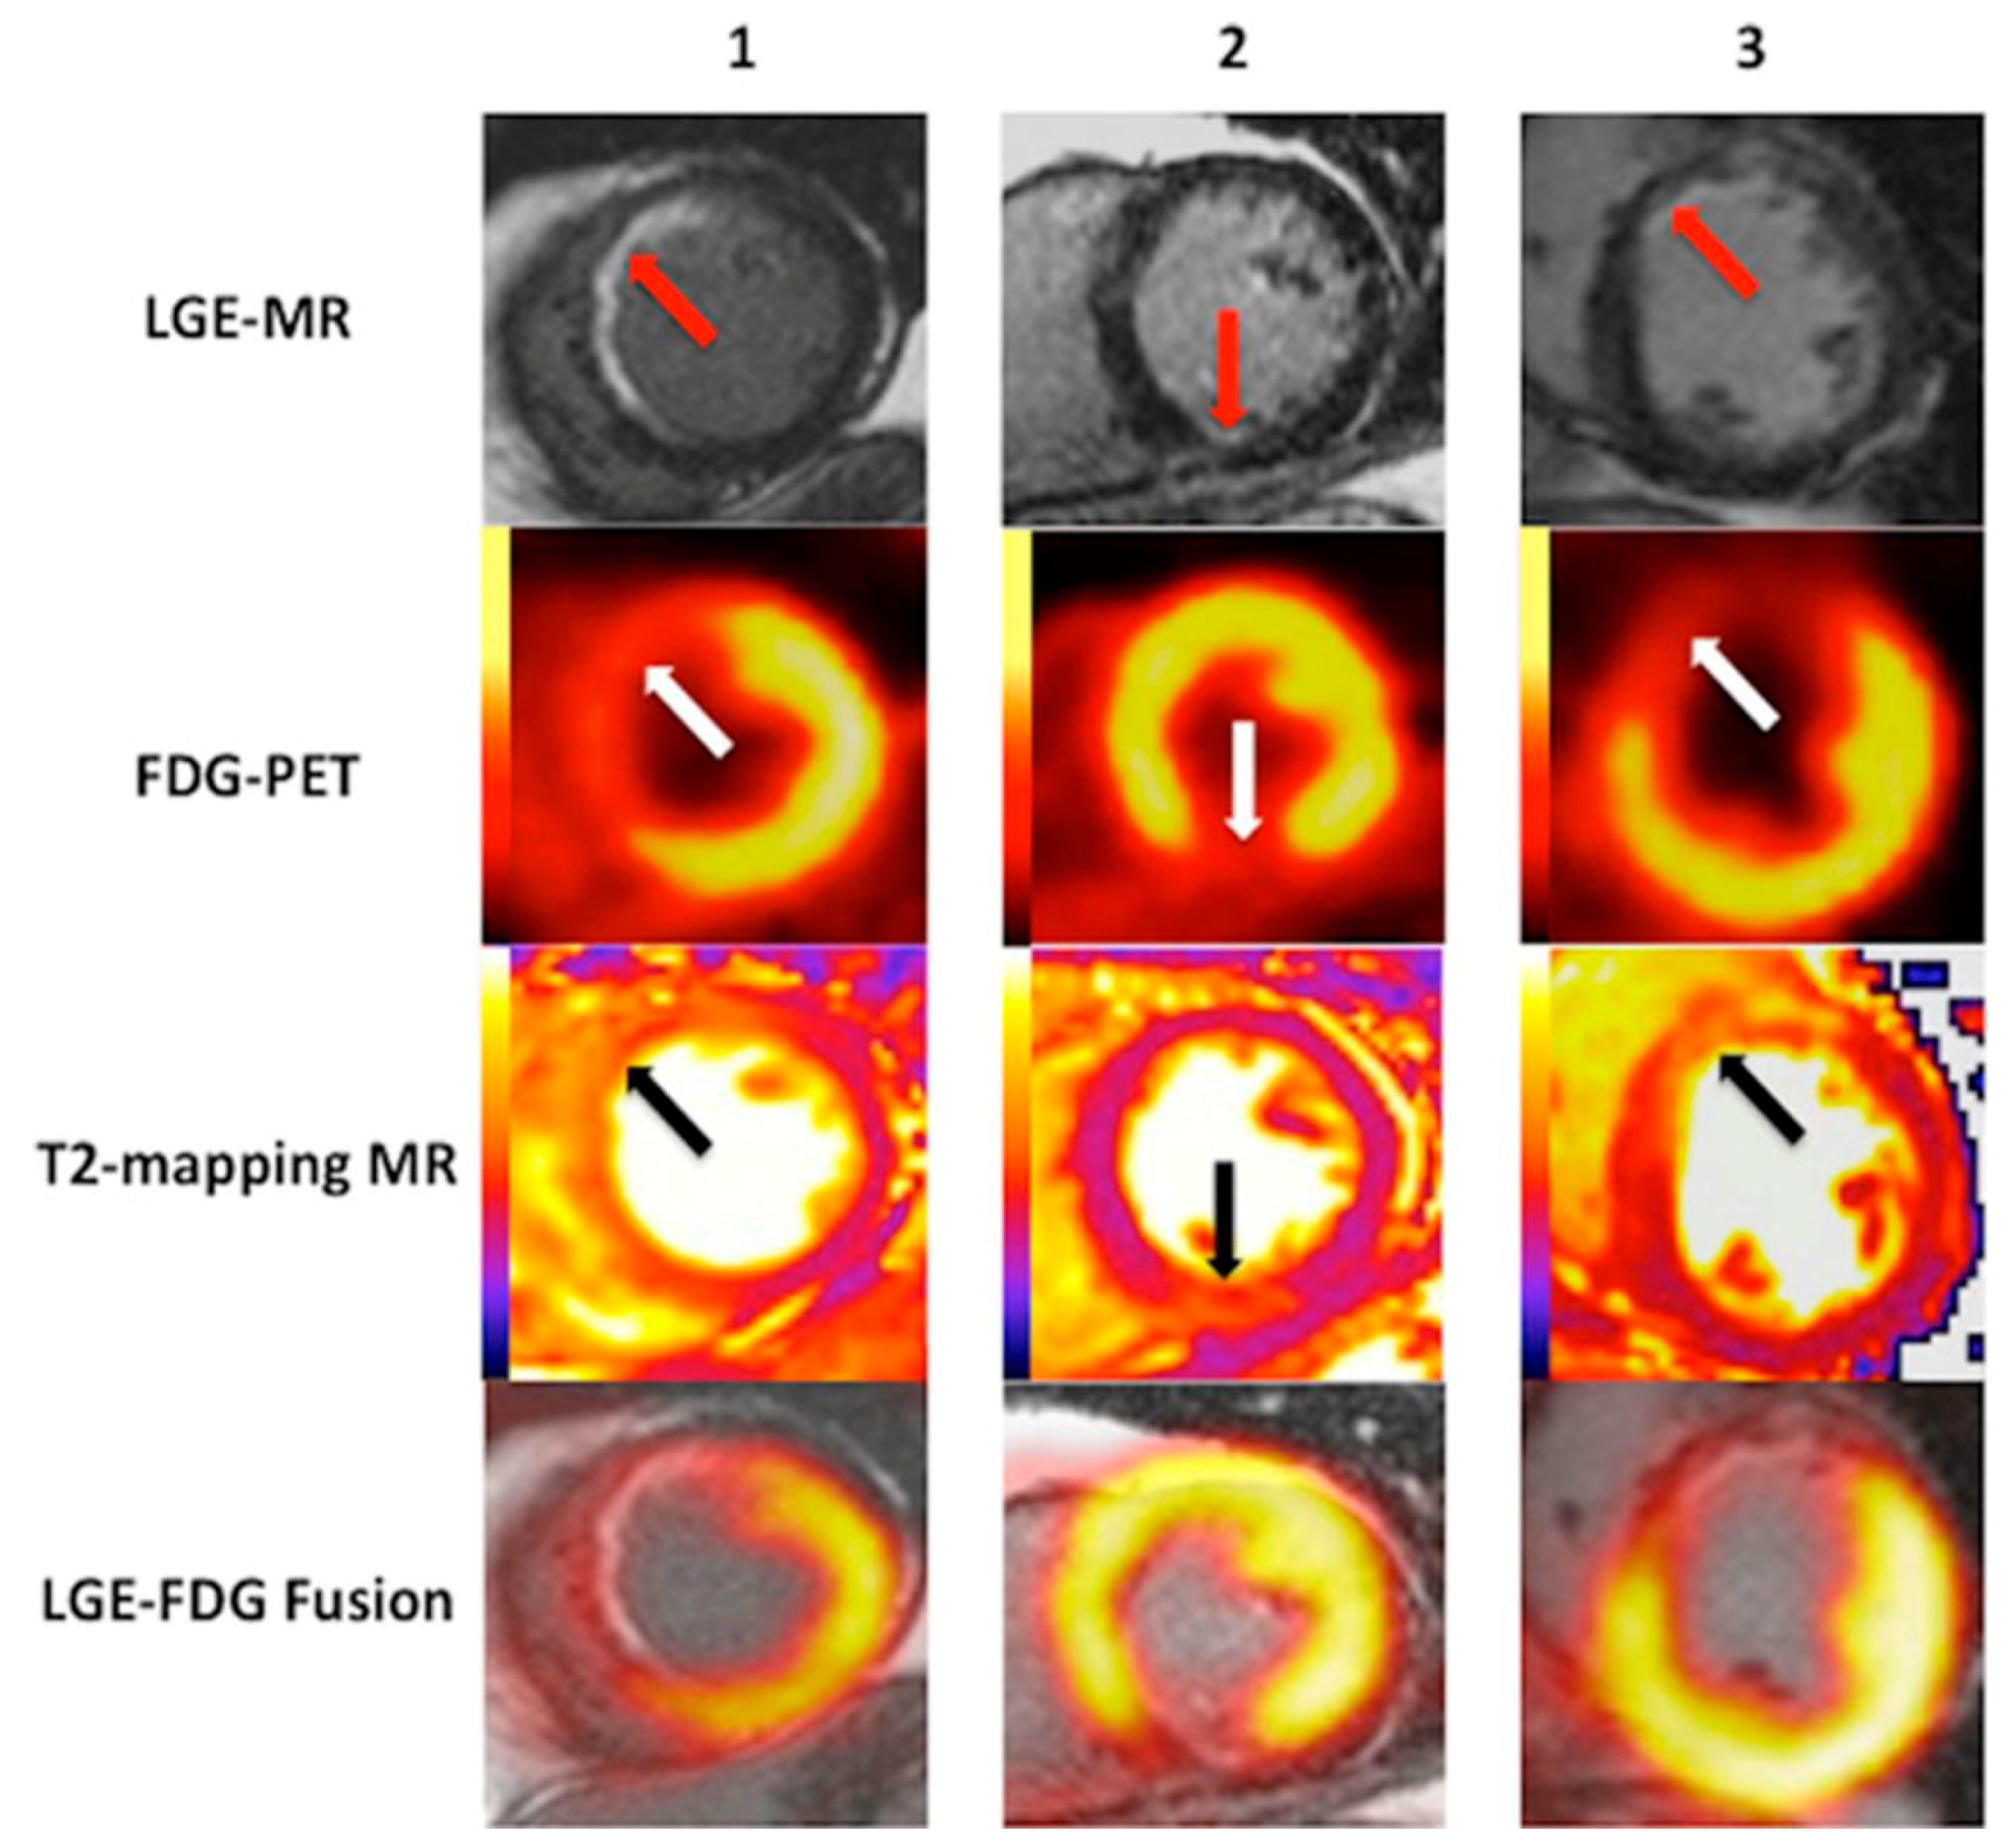

- Bulluck, H.; White, S.K.; Fröhlich, G.M.; Casson, S.G.; O’Meara, C.; Newton, A.; Nicholas, J.; Weale, P.; Wan, S.M.Y.; Sirker, A.; et al. Quantifying the area at risk in reperfused ST-Segment–Elevation myocardial infarction patients using hybrid cardiac positron emission tomography–magnetic resonance imaging. Circ. Cardiovasc. Imaging 2016, 9, e003900. [Google Scholar] [CrossRef] [PubMed]